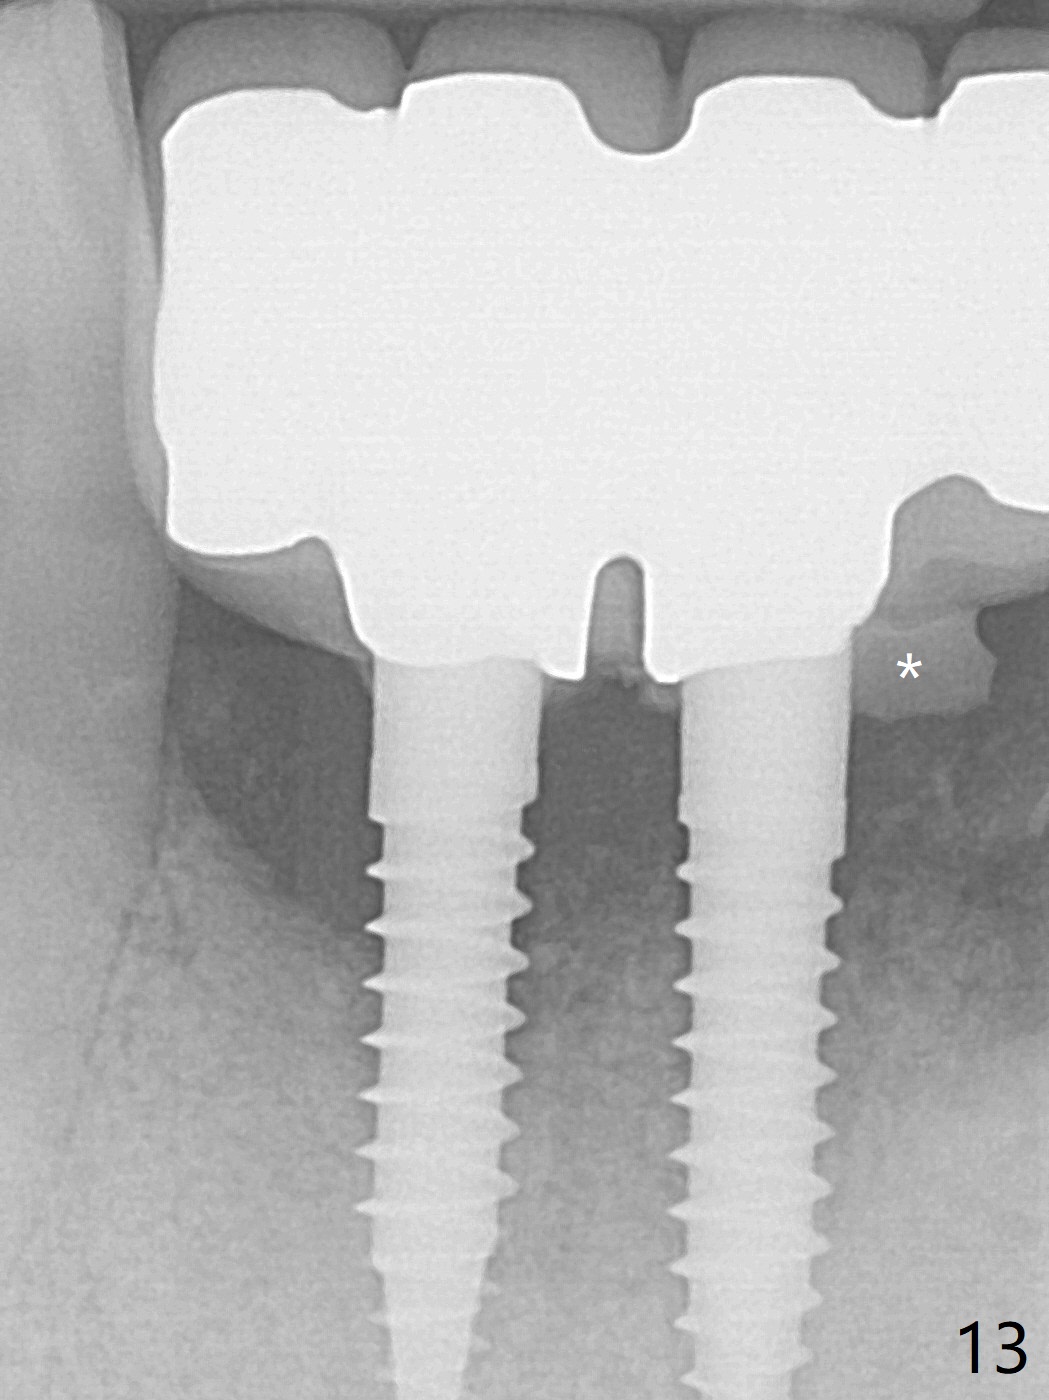

When the patient (smoker) returns for treatment, the apical abscess associated with #25 and 26 reduces with oral Amoxicillin. He agrees with 4 incisor extraction because of 2 apical fistulae (Fig.1 >). Osteotomy starts at the central incisor sockets due to mesial root exposure of the canines (Fig.2 arrowheads) and buccal alveolar bone fracture between #23 and 24 (Fig.7). Two of 3x14(4) mm 1-piece implants are placed with ~ 2 mm buccal gap (Fig.3). After Vanilla graft is placed in the bony defects (Fig.5 *) and Osteogen plug, sutures are placed (Fig.4). The implants are then placed deep to decrease thread exposure (Fig.6). Periodontal dressing is applied instead of provisional. Alveolar bone fracture between #23 and #24 accounts for why an implant is less suitably placed at #24 (Fig.7). Three months postop, composite is added to the pontic areas of the provisional (Fig.8 *). When the provisional is seated, the convex pontics press the used-to-be-flat gingiva (Fig.9 arrows). Thus the concave gingiva forms (Fig.10 *) with corresponding papillae (^). In fact the photos of Fig.8-10 is taken ~3 weeks later. Most of the grafted bone remains in place 3.5 months postop (Fig.11). A piece of floss with 2 knots in one end is placed between the middle units of the final bridge before cementation (Fig.12 (4 months 10 days postop)). In fact removal of residual cement is not so simple. It is tedious (Fig.13,14). An asymptomatic buccal fenetration with implant thread exposure is found 2 months post cementation and persists for another month in spite of advice to reduce smoking (1/2 ppd) and use of water pik (Fig.15). The area will be debrided, followed by bone graft and PRF in a month.